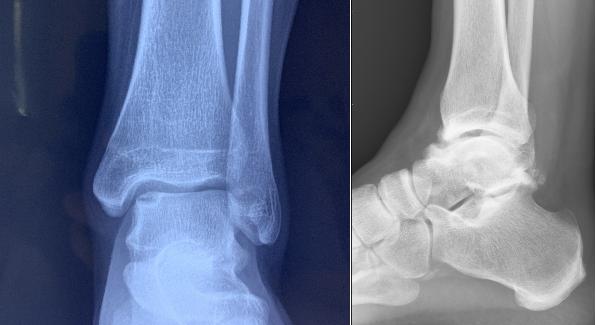

从 X 光片上,我们只能看到踝关节的骨性的结构,这也是为什么有时候医生会要求再做核磁共振的检查来看看踝关节的周围,韧带、肌肉以及肌腱的情况。

踝关节,主要由 3 块骨头组成:胫骨(下肢的主要负重骨)、腓骨(下肢的次要负重骨及韧带、肌肉的附着区)、距骨(足的第二大骨)。

参考上图,我们可以将人的踝关节想象成一个正在骑马的人,胫骨和腓骨就像是人的两条腿一样,骑跨在有着「马鞍」一样关节面的距骨上。